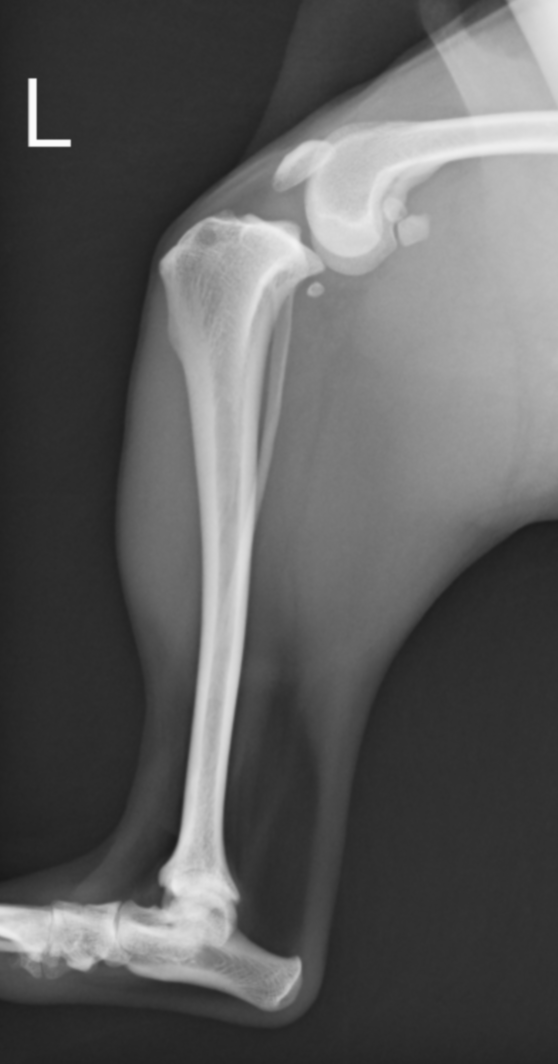

前十字靭帯損傷の膝。大腿骨が尾側に滑り、脛骨の前方変位が認められる

正常肢。大腿骨と脛骨の位置関係が前十字靭帯損傷時と異なり、しっかり連絡性がある